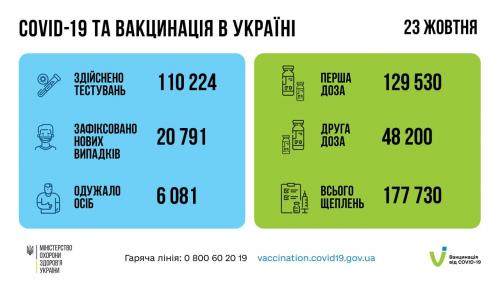

МОЗ: Уперше з початку пандемії було зроблено понад 100 тисяч ПЛР-досліджень за добу